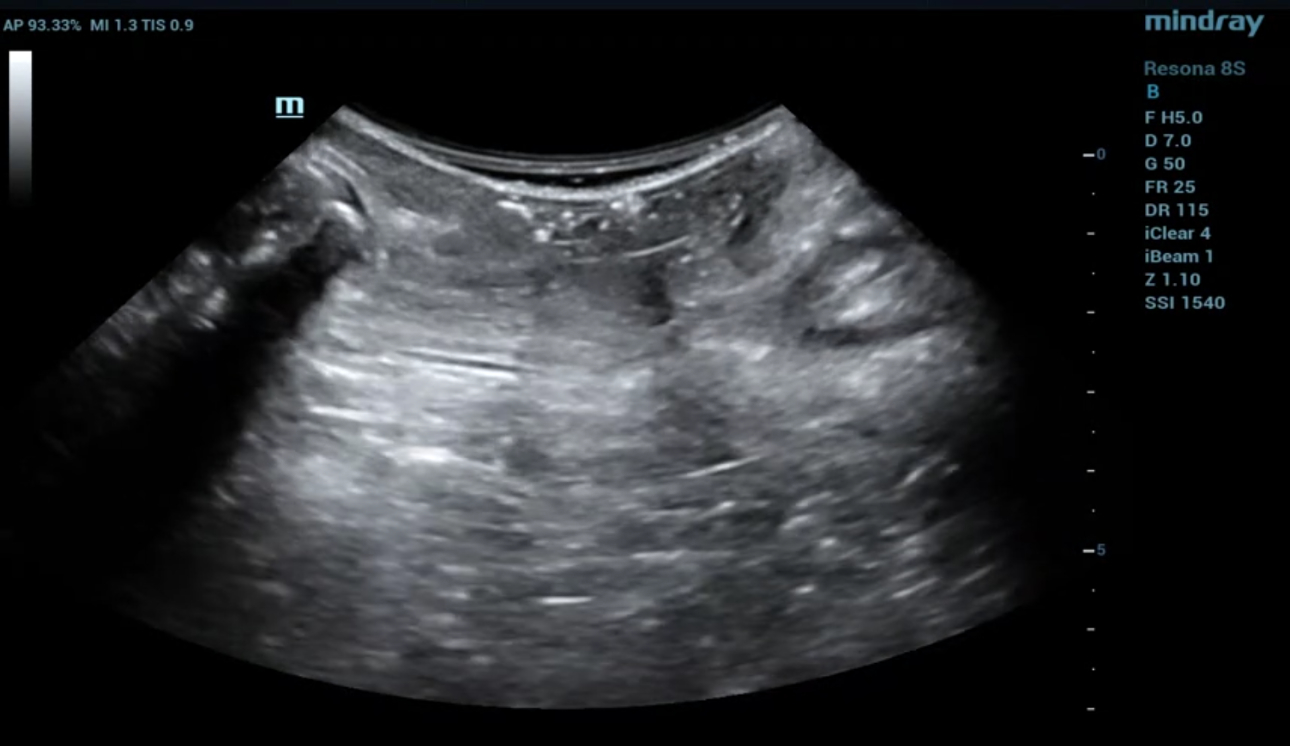

?? ?? ????? parasagittal view??? ???/?? 2D ???, 3D/4D ?? ??, Ipage+?? ?? ?? ?? ???? ?????.

- 2D ?? : ???? ??? ?? ?? ???? interruption? ?? ???? ??? ?? ??? ??.

- Levator hiatus? ?????? ?? ????? ?? ??.